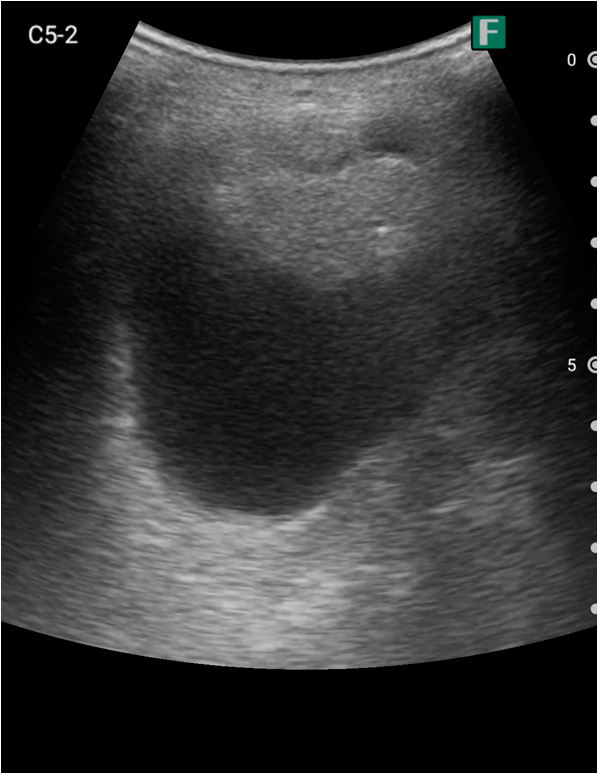

実際に、私がiViz airを使用した具体例を2つ紹介します。1つ目は救急外来での事例です。

夜間、腹痛を主訴に高齢の男性が救急外来にいらっしゃいました。その方は尿道カテーテルが入っており、頻繁にカテーテルの閉塞を起こしている病歴がありました。

視診を行い下腹部に軽度の膨隆が確認できましたが体外から出ているカテーテルには明らかな閉塞を認めませんでした。そこで、iViz airで観察したところ、膀胱内に約400mlの残尿を認めカテーテル閉塞による腎後性腎不全と診断を確定させることができました。尿道カテーテルを抜去した際、外見からは見えないカテーテルの先端部分に沈殿物を認め、閉塞の原因であるとわかりました。その後尿道カテーテルの交換を行うと残尿の排出ともに腹痛は消失し、無事に帰宅されました。iViz airでの観察が尿閉の確定診断につながった症例です。